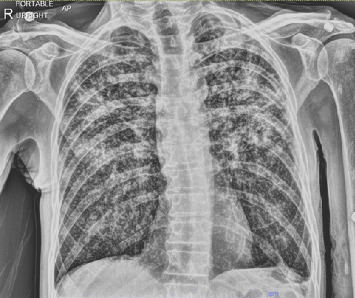

Spread of Mycobacterium tuberculosis (MTB) to the larynx is exceedingly rare and can be obscured by more common conditions such as laryngeal cancer or oropharyngeal candidiasis, complicating an accurate diagnosis. Risk factors for chronic laryngeal disease, such as smoking and toxin exposure, place TB infection comparatively lower for consideration on a physician's differential. However, identifying these lesions is crucial from a medical and public health perspective to prevent community spread. We report the case of a 60-year-old male who presented with dysphonia, pharyngitis, aphasia, and significant unintentional weight loss. X-rays demonstrated focal opacities in the upper lung lobes. Laryngoscope biopsy revealed caseating granulomas and a positive culture for MTB. Laryngeal TB presents as a suspicious throat mass with nonspecific symptoms and should be thoroughly investigated by clinicians.